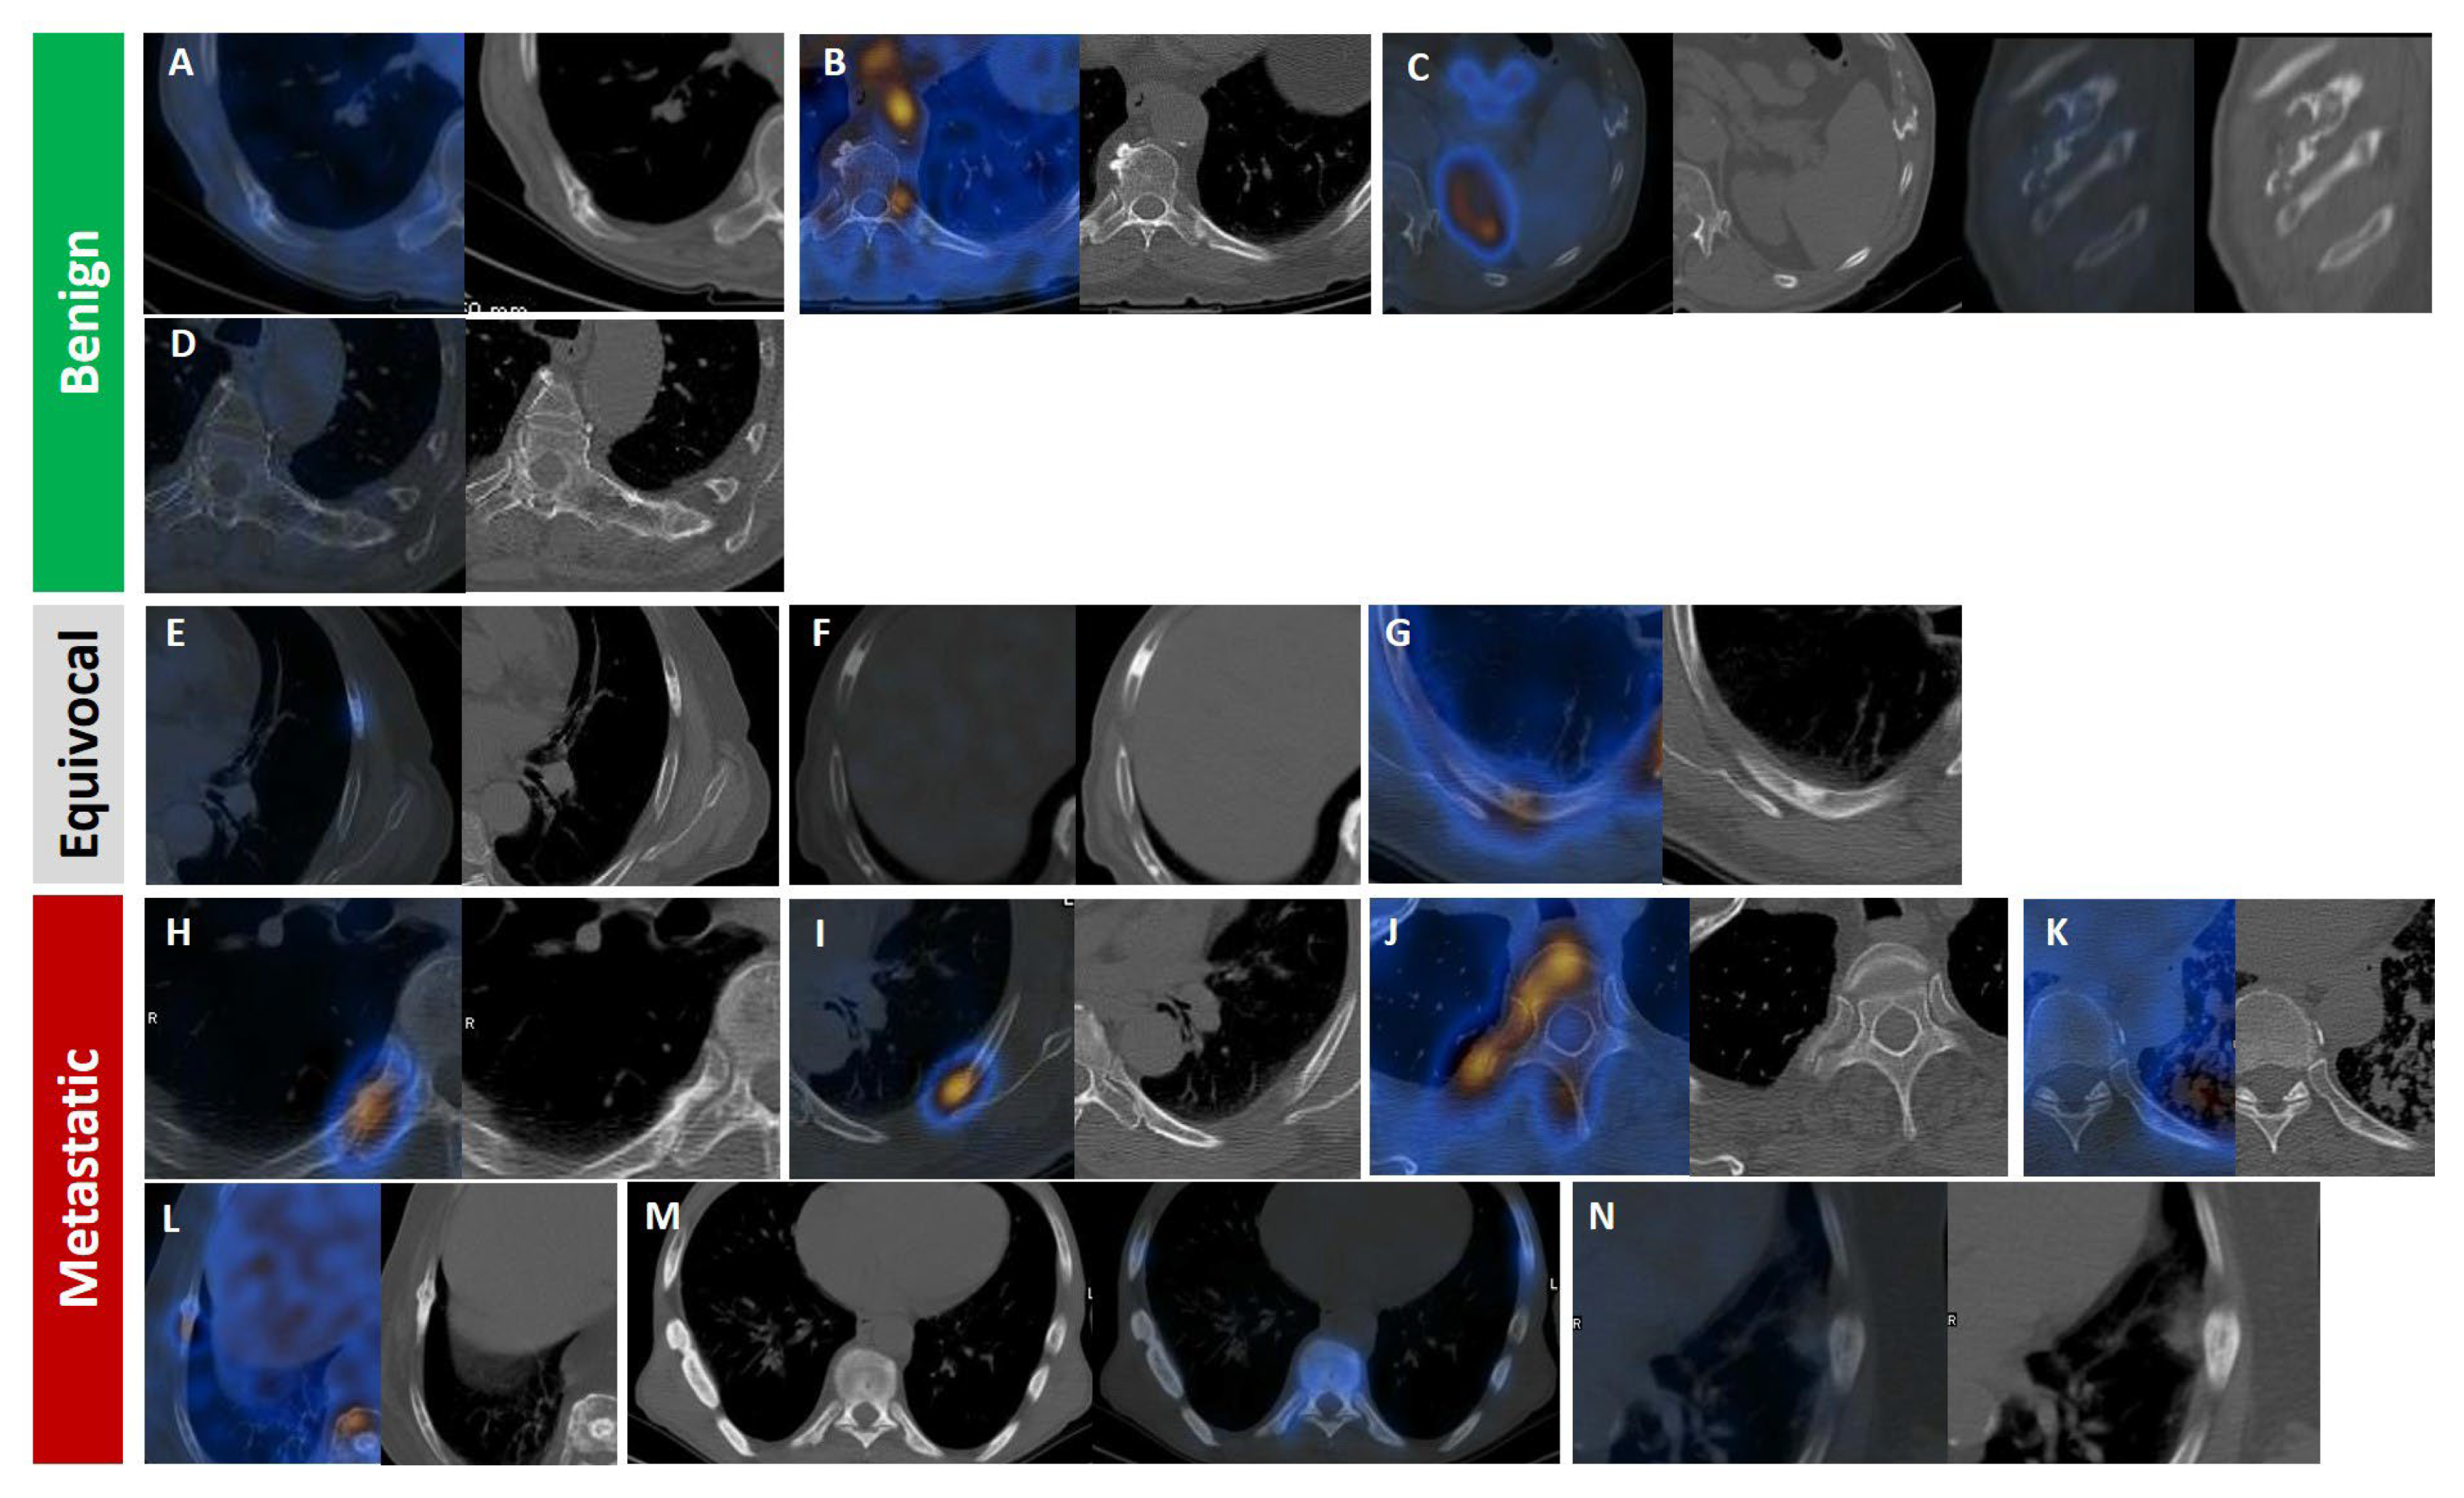

| Factor | Description | Benign Characteristics | Metastatic Characteristics | Diagnosis Utility | Pitfalls |

|---|---|---|---|---|---|

| Radiotracer Uptake Intensity | Standardized uptake value maximum on PSMA PET/CT | Low-moderate (<10); often < liver uptake | High (>10); typically > liver uptake | Predicts malignancy likelihood; guides radioligand therapy | Tracer variability (18F-PSMA-1007 higher unspecific uptake); no standardized cutoff |

| Number of Lesions | Number of PSMA-avid rib lesions | Solitary (98% benign if isolated) | Multiple (97–98% associated with polymetastatic disease) | Indicates disease extent; solitary lesions often benign | Rare isolated metastases (2–3%); needs correlation with other sites |

| Location | Rib lesion site | Posterior ribs (often degenerative) | Anterior/lateral ribs (higher malignancy risk) | Guides biopsy prioritization | Limited data on site-specific malignancy rates |

| CT Morphology or Bone Scan | Structural features on CT (lytic or sclerotic) | Normal or degenerative | Lytic or sclerotic lesions; cortical disruption | Enhances specificity when combined with PSMA uptake | Non-specific findings |

| Patient-Specific Factors | Patient-specific factors (such as PSA and Gleason score) | Low PSA (<10 ng/mL); Gleason <7 | High PSA (>20 ng/mL); Gleason ≥8 | Contextualizes imaging; high-risk features suggest metastases | Non-specific; overlap in early disease |

| Changes Over Time | Longitudinal changes on serial PSMA PET/ | Stable SUVmax, no new lesions; often degenerative or post-traumatic | Increasing SUVmax (>20% rise), new lesions, or morphological progression | Indicates disease progression; guides therapy adjustment | Requires serial imaging; limited data on optimal intervals; benign changes (such as healing fractures) may mimic progression |

| Tracer Type | PSMA ligand used (18F-PSMA-1007 vs. 68Ga-PSMA-11) | 18F-PSMA-1007: higher unspecific bone uptake (20% equivocal) | 68Ga-PSMA-11: lower unspecific uptake; higher specificity | Influences diagnostic accuracy; 68Ga-PSMA-11 preferred for rib lesions | 18F-PSMA-1007 increases false positives; protocol variability |